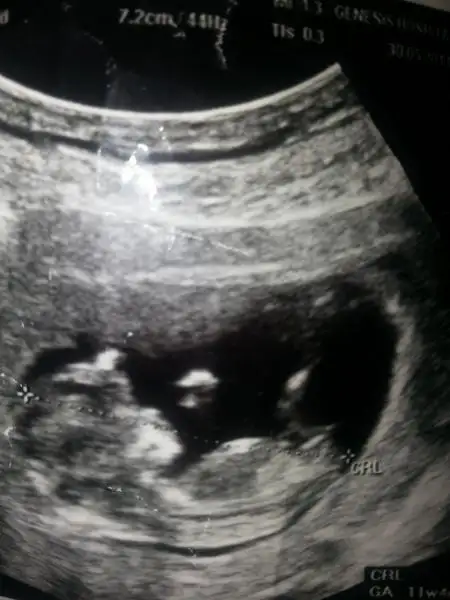

dr soylemeden siz gorun genital nub teorisi ( bebegin cinsiyeti)

Yok aslında çok tecrübeli değil genç bir doktor...sordum da onlarda genital nub kemiğine göre tahminde bulunuyorlarmış 16 dan önce kesin olmazmış 16 dan sonra organ görülüyormuş 16 ya kadar tahmin edilir sadece dedi...%70 kız dedi canım dr bize.... prenses geliyor evimize :)) 483. Ncü sayfada var fotomuz kemik gerçekten paralel duruyor

Dilco erkek bebegin

Rocechina bebegin kiz cnm

Esmiii bebegin erkek nubun ucu yukarda cunku :)